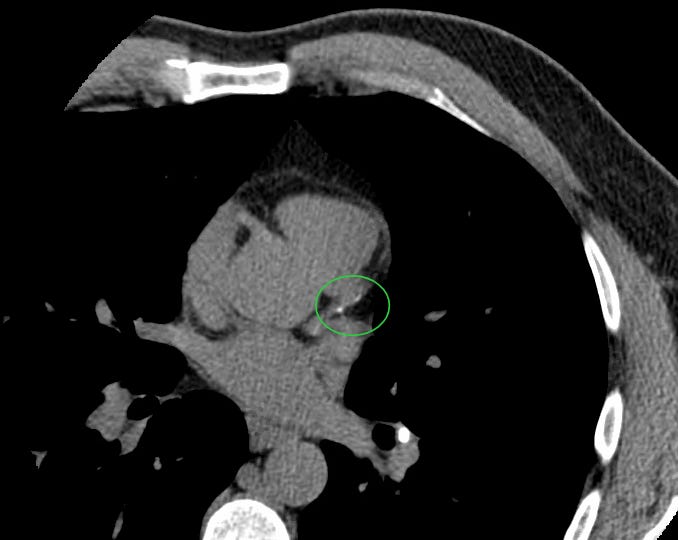

I recommended the patient get a coronary artery calcium (CAC) scan to look for early coronary plaque and this demonstrated two small calcific plaques in the proximal portion of his LAD coronary artery (inside the green circle.)

His calcium score was 9 which is higher than 82% of 45-year-old white males.